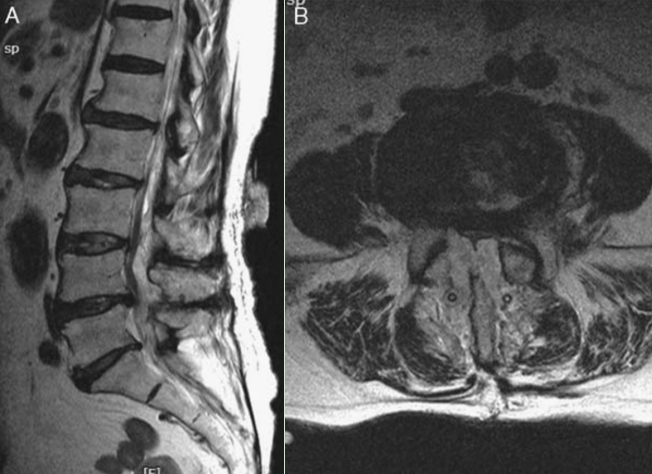

1 MRI显示腰椎术后SEH形成

血肿形成是腰椎术后早期严重并发症,一般发生在术后1~2d,符合手术指征者应当立即探查切口、清除血肿。血肿一般位于手术切口部位,部分无症状患者血肿可自行吸收,而一些患者则表现为切口剧烈疼痛,若压迫神经还可出现肌力下降和感觉减退,但因血肿部位不同,神经损伤表现也有所不同。其中硬膜外血肿(spinal epidural hemorrhageSEH)进展迅速,对脊髓压迫时间越长,脊髓损伤越重,严重者可导致瘫痪。

SSI外,SEH也是脊柱退行性疾病URP的主要原因。Shimizu等发现9335例脊柱退行性疾病患者中有33例因SEH再次手术。Zijlmans等报道1333例腰椎退行性疾病患者接受单节段或双节段腰椎间盘切除术或腰椎板切除术,术后2例发生SEH,并伴随明显神经功能损伤,因此再次手术清除血肿。Yi等对3720例患者临床资料进行回顾性研究,发现3例腰椎管狭窄症和1例腰椎间盘突出症患者因SEH严重损伤神经再次手术。Aihara等调查了394例显微内镜腰椎减压手术患者,发现3例因SEH再次手术。Snopko等调查了371例腰椎退行性疾病患者,发现7例减压手术后因SEH再次手术。Mueller等以1 004例腰椎退行性疾病患者为研究对象,行微创腰椎椎板切除术或椎板切开术进行减压后,有14例因SEH再次手术,其中9例神经功能受损。Tsai等提出,相比于其他并发症,SEH更易导致神经损伤,其研究中10 350例患者有27例因SEH合并神经损伤再次手术,其中20例术后神经功能得到改善,但仍有7例未改善。Khalifa等的研究共纳入51例接受腰椎融合术的患者,发现2例因皮下血肿再次手术。

此外,目前已经证实输血、多节段手术和肥胖是SEH的危险因素。也有学者提出抗凝剂、术前凝血值异常和吸烟是脊柱术后SEH的独立危险因素。